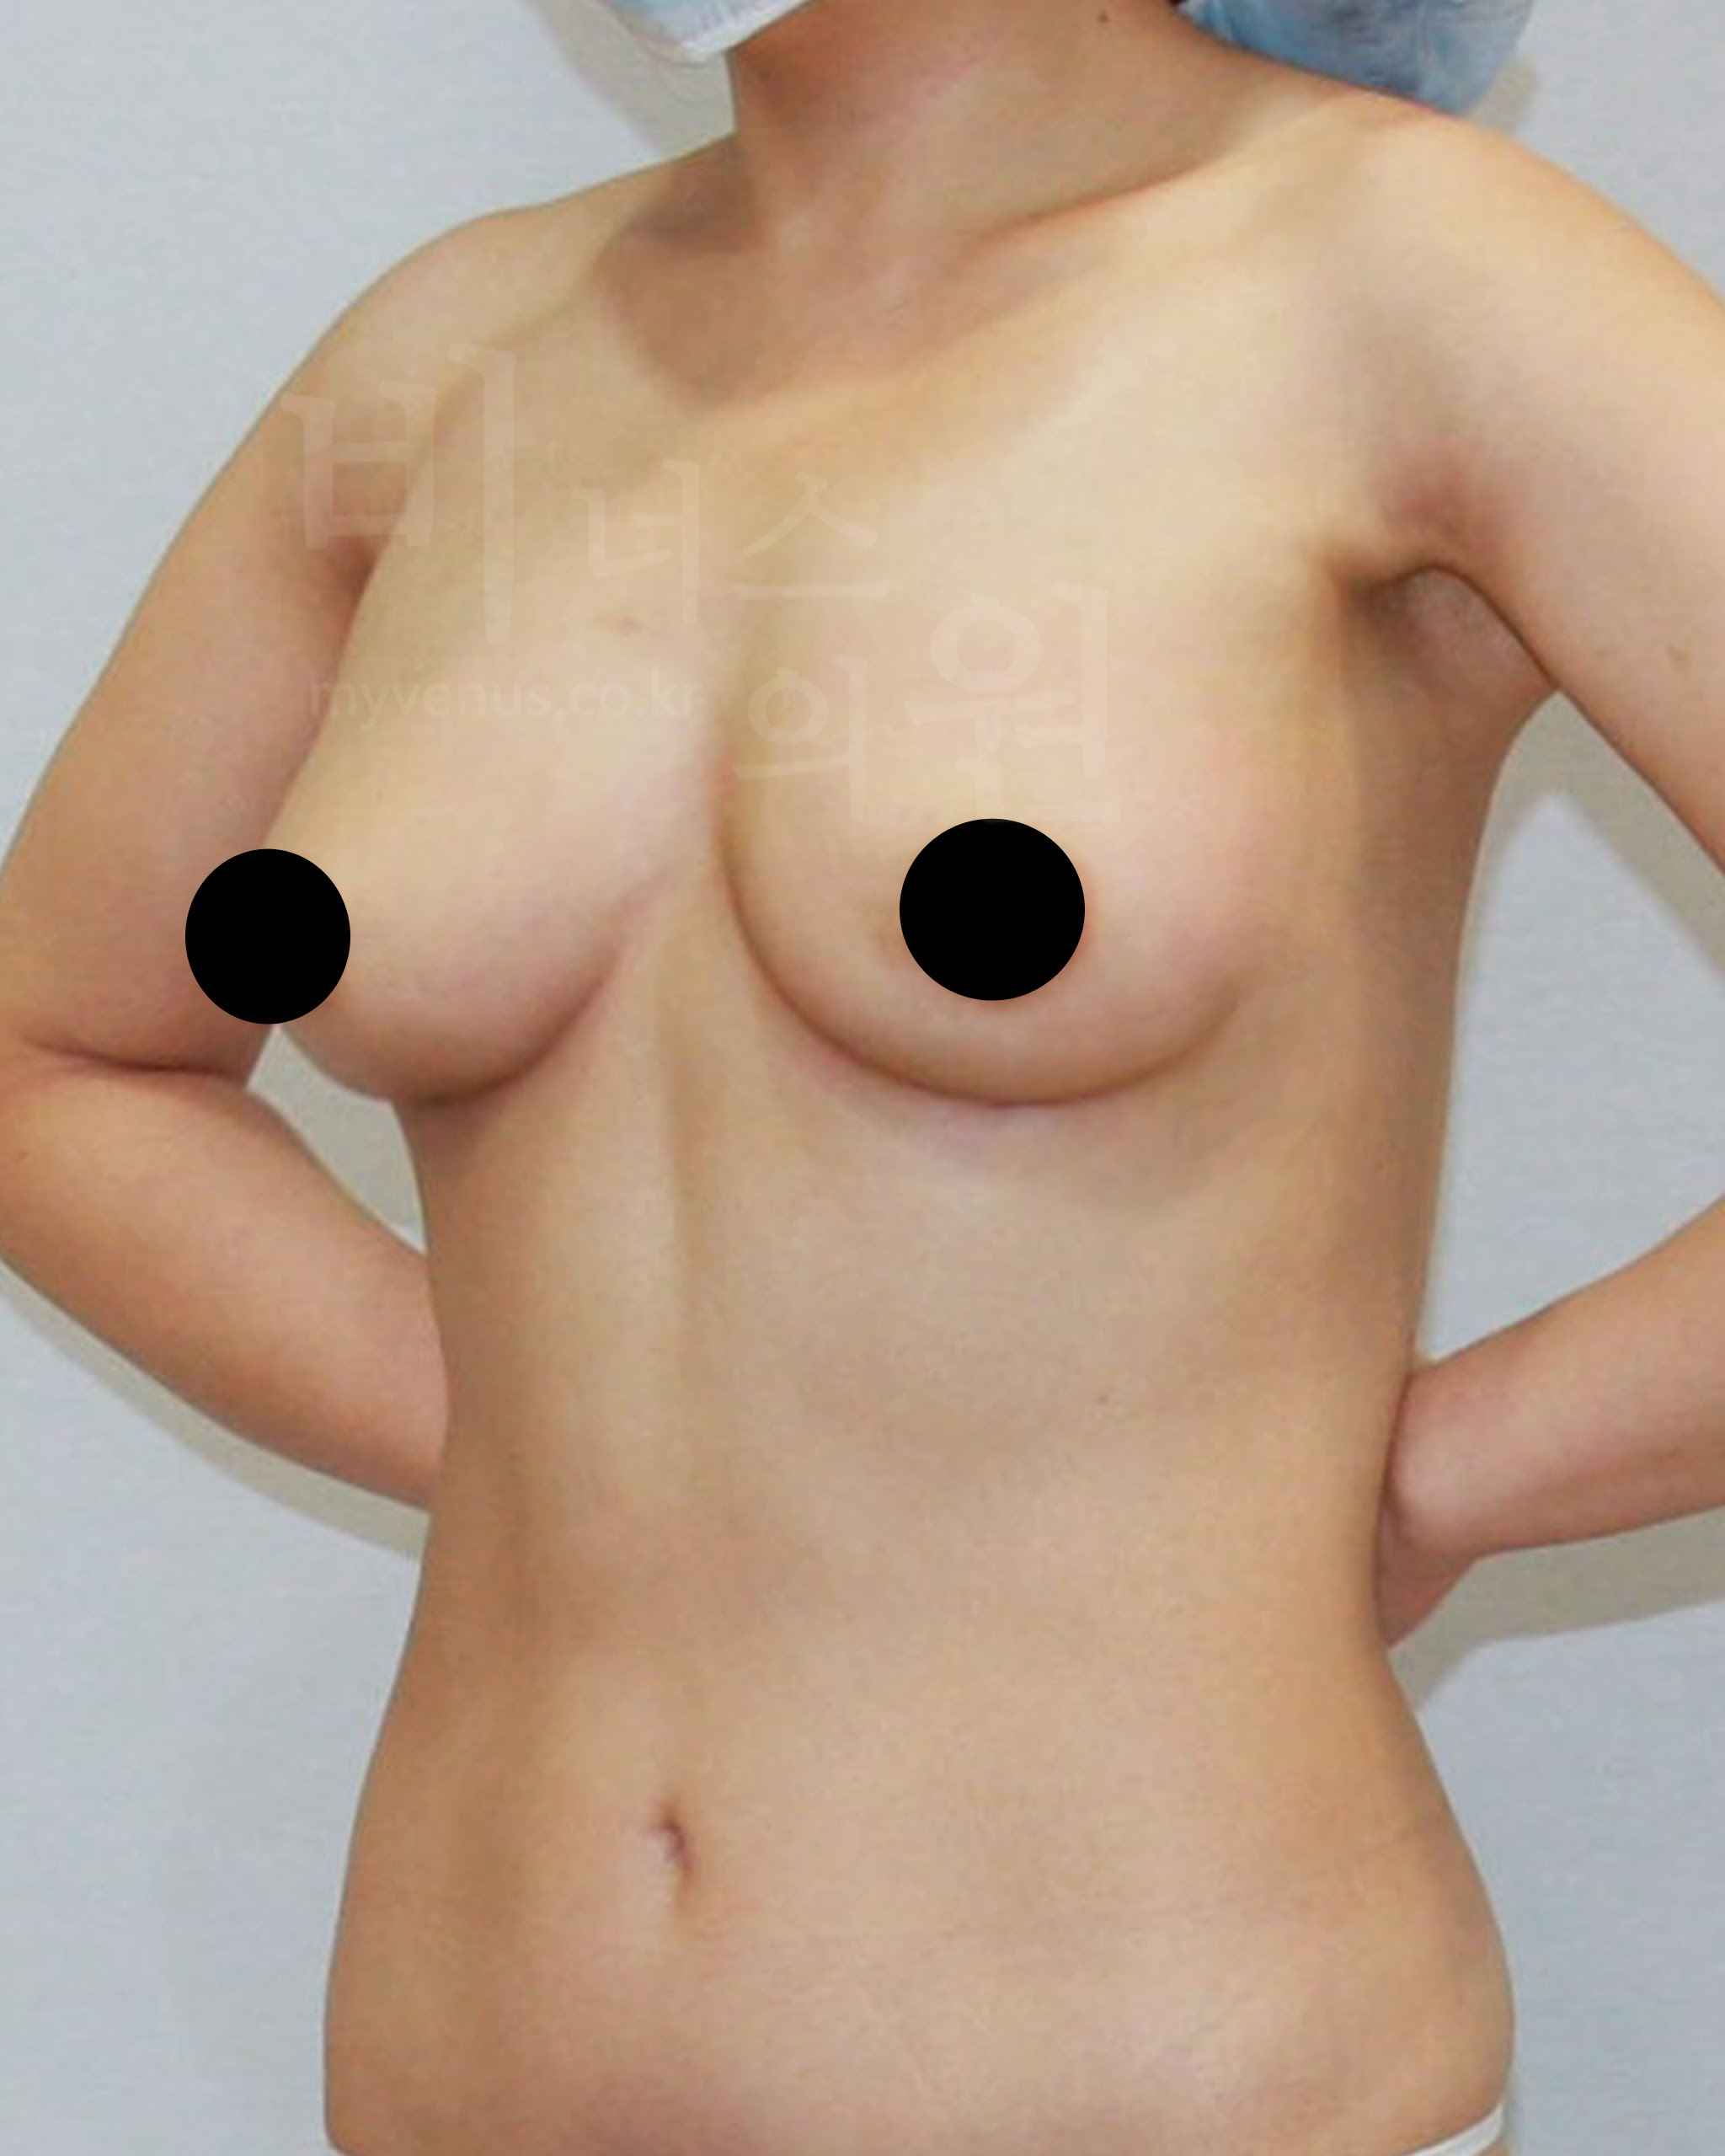

가슴축소 지방흡입 전 사진

처진 정도가 유방 길이로 보여지는 모습

가슴축소 지방흡입 후 사진

사이즈 감소와 유방 길이가 짧아진 모습

가슴축소 지방흡입은 저렴한 비용으로 흉터나 수술 후의 부작용, 합병증 걱정 없이 큰 가슴의 고통에서 벗어나 볼륨 있고 예쁜 가슴을 만들 수 있어요. 측면의 모습에서 가슴 안쪽의 유방 선이 길게 늘어져 있던 모습이였으나 처짐 없이 볼륨 업된 사이즈 감소가 이루어지면서 가슴 선이 짧아 졌어요.